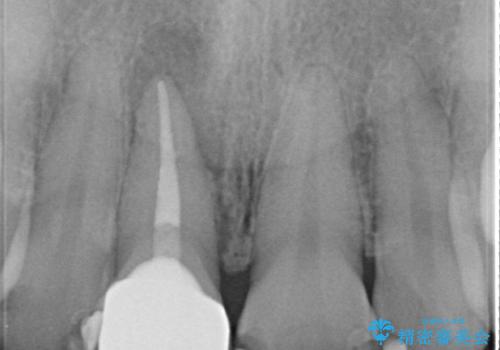

- 右上1番目の歯の変色が気になると来院された方の症例です。

検査の結果、右上1の歯は失活(歯の神経が死んでいること)していたため根管治療を行いました。

その後オールセラミッククラウン(スペシャル)による補綴を行いました。

なお隣在歯の樹脂は今後治療していく予定です。